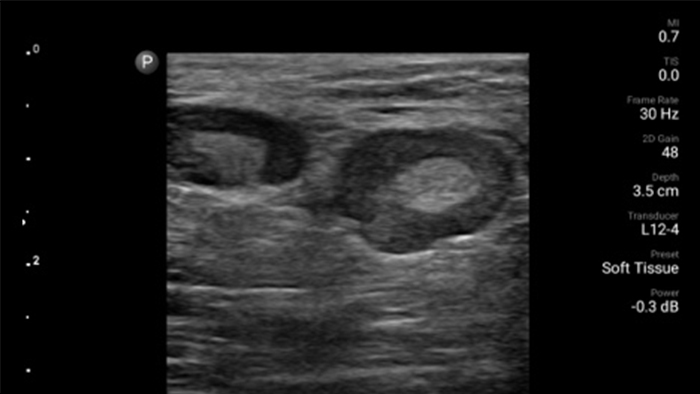

Reduzca las complicaciones en procedimientos guiados por aguja

El ultrasonido portátil Lumify para anestesiología le ayuda a visualizar claramente la definición de los bordes con la colocación de la aguja, los nervios circundantes, los vasos sanguíneos y los planos fasciales.